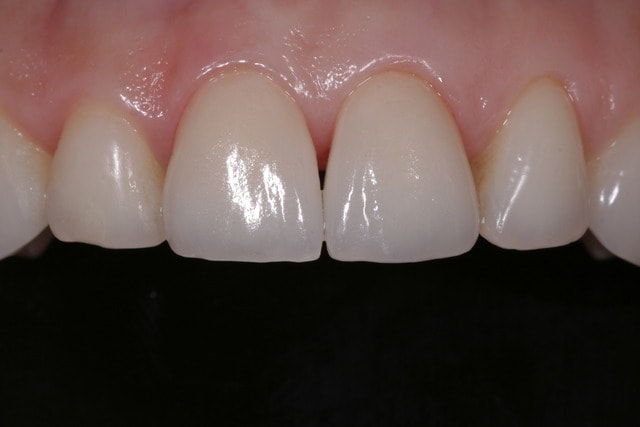

Allez petit quizz, photos de 2 emax ce matin avec un Canon 450D objectif sigma 105mm f20/250.

Quelle différence entre les deux photos?

En fait la différence viens de l'orientation des sources lumineuses. En les gardant à droite et à gauche de l'objectif on à un forte signature du flash sur les reliefs verticaux de la dent (il y a plus de relief et on accentue le phénomène en mettant des réglages d'intensité différents) alors qu'en orientant les sources en haut et en bas, on a moins de signature (c'est mieux pour un relevé de teinte) mais aussi moins de relief.

Conclusion, dans les cas d'esthétique je prend toujours plusieurs clichés avec différents réglages et différentes orientations et on garde le meilleur, il suffit juste de choisir mais là je pense qu'on ne garderait pas tous le même...